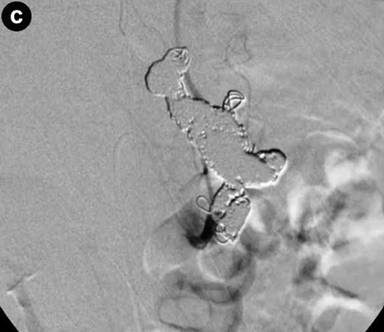

An emergency intervention was then carried out. Angiography clearly revealed a fusiform aneurysm of the middle-distal splenic artery and narrowing of the proximal splenic artery (Figure 4a). All parts of the splenic artery were successfully coil-embolized (Figure 4b). Twenty days later, intervention for dissection of the celiac artery was performed. The celiac artery including the false lumen was successfully coil-embolized (Figure 4c). The patient has since shown no recurrence of the epigastric pain or melena.

Figure 4. a. Angiography of the celiac artery clearly showing the narrowing of the proximal splenic artery (small arrow) and a fusiform aneurysm of the middle-distal splenic artery (large arrow). b. Angiography of the celiac artery showing that all parts of the splenic artery were successfully coil-embolized. c. Lateral angiography of the celiac artery showing that the celiac artery including the false lumen was successfully coil-embolized. |